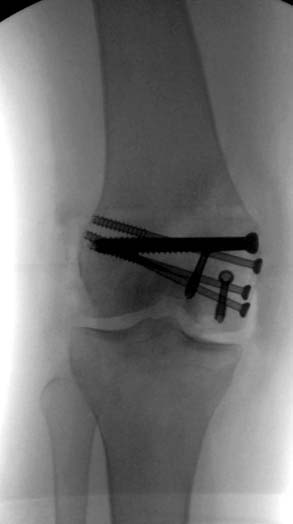

[Ortho] Нелеченный перелом Hoffa

Здесь представлены различные варианты фиксации перелома, а также снимки

комбинации перелома с повреждением хряща (12-19). Пластика хряща

OsseoFit и установка custom made plate.